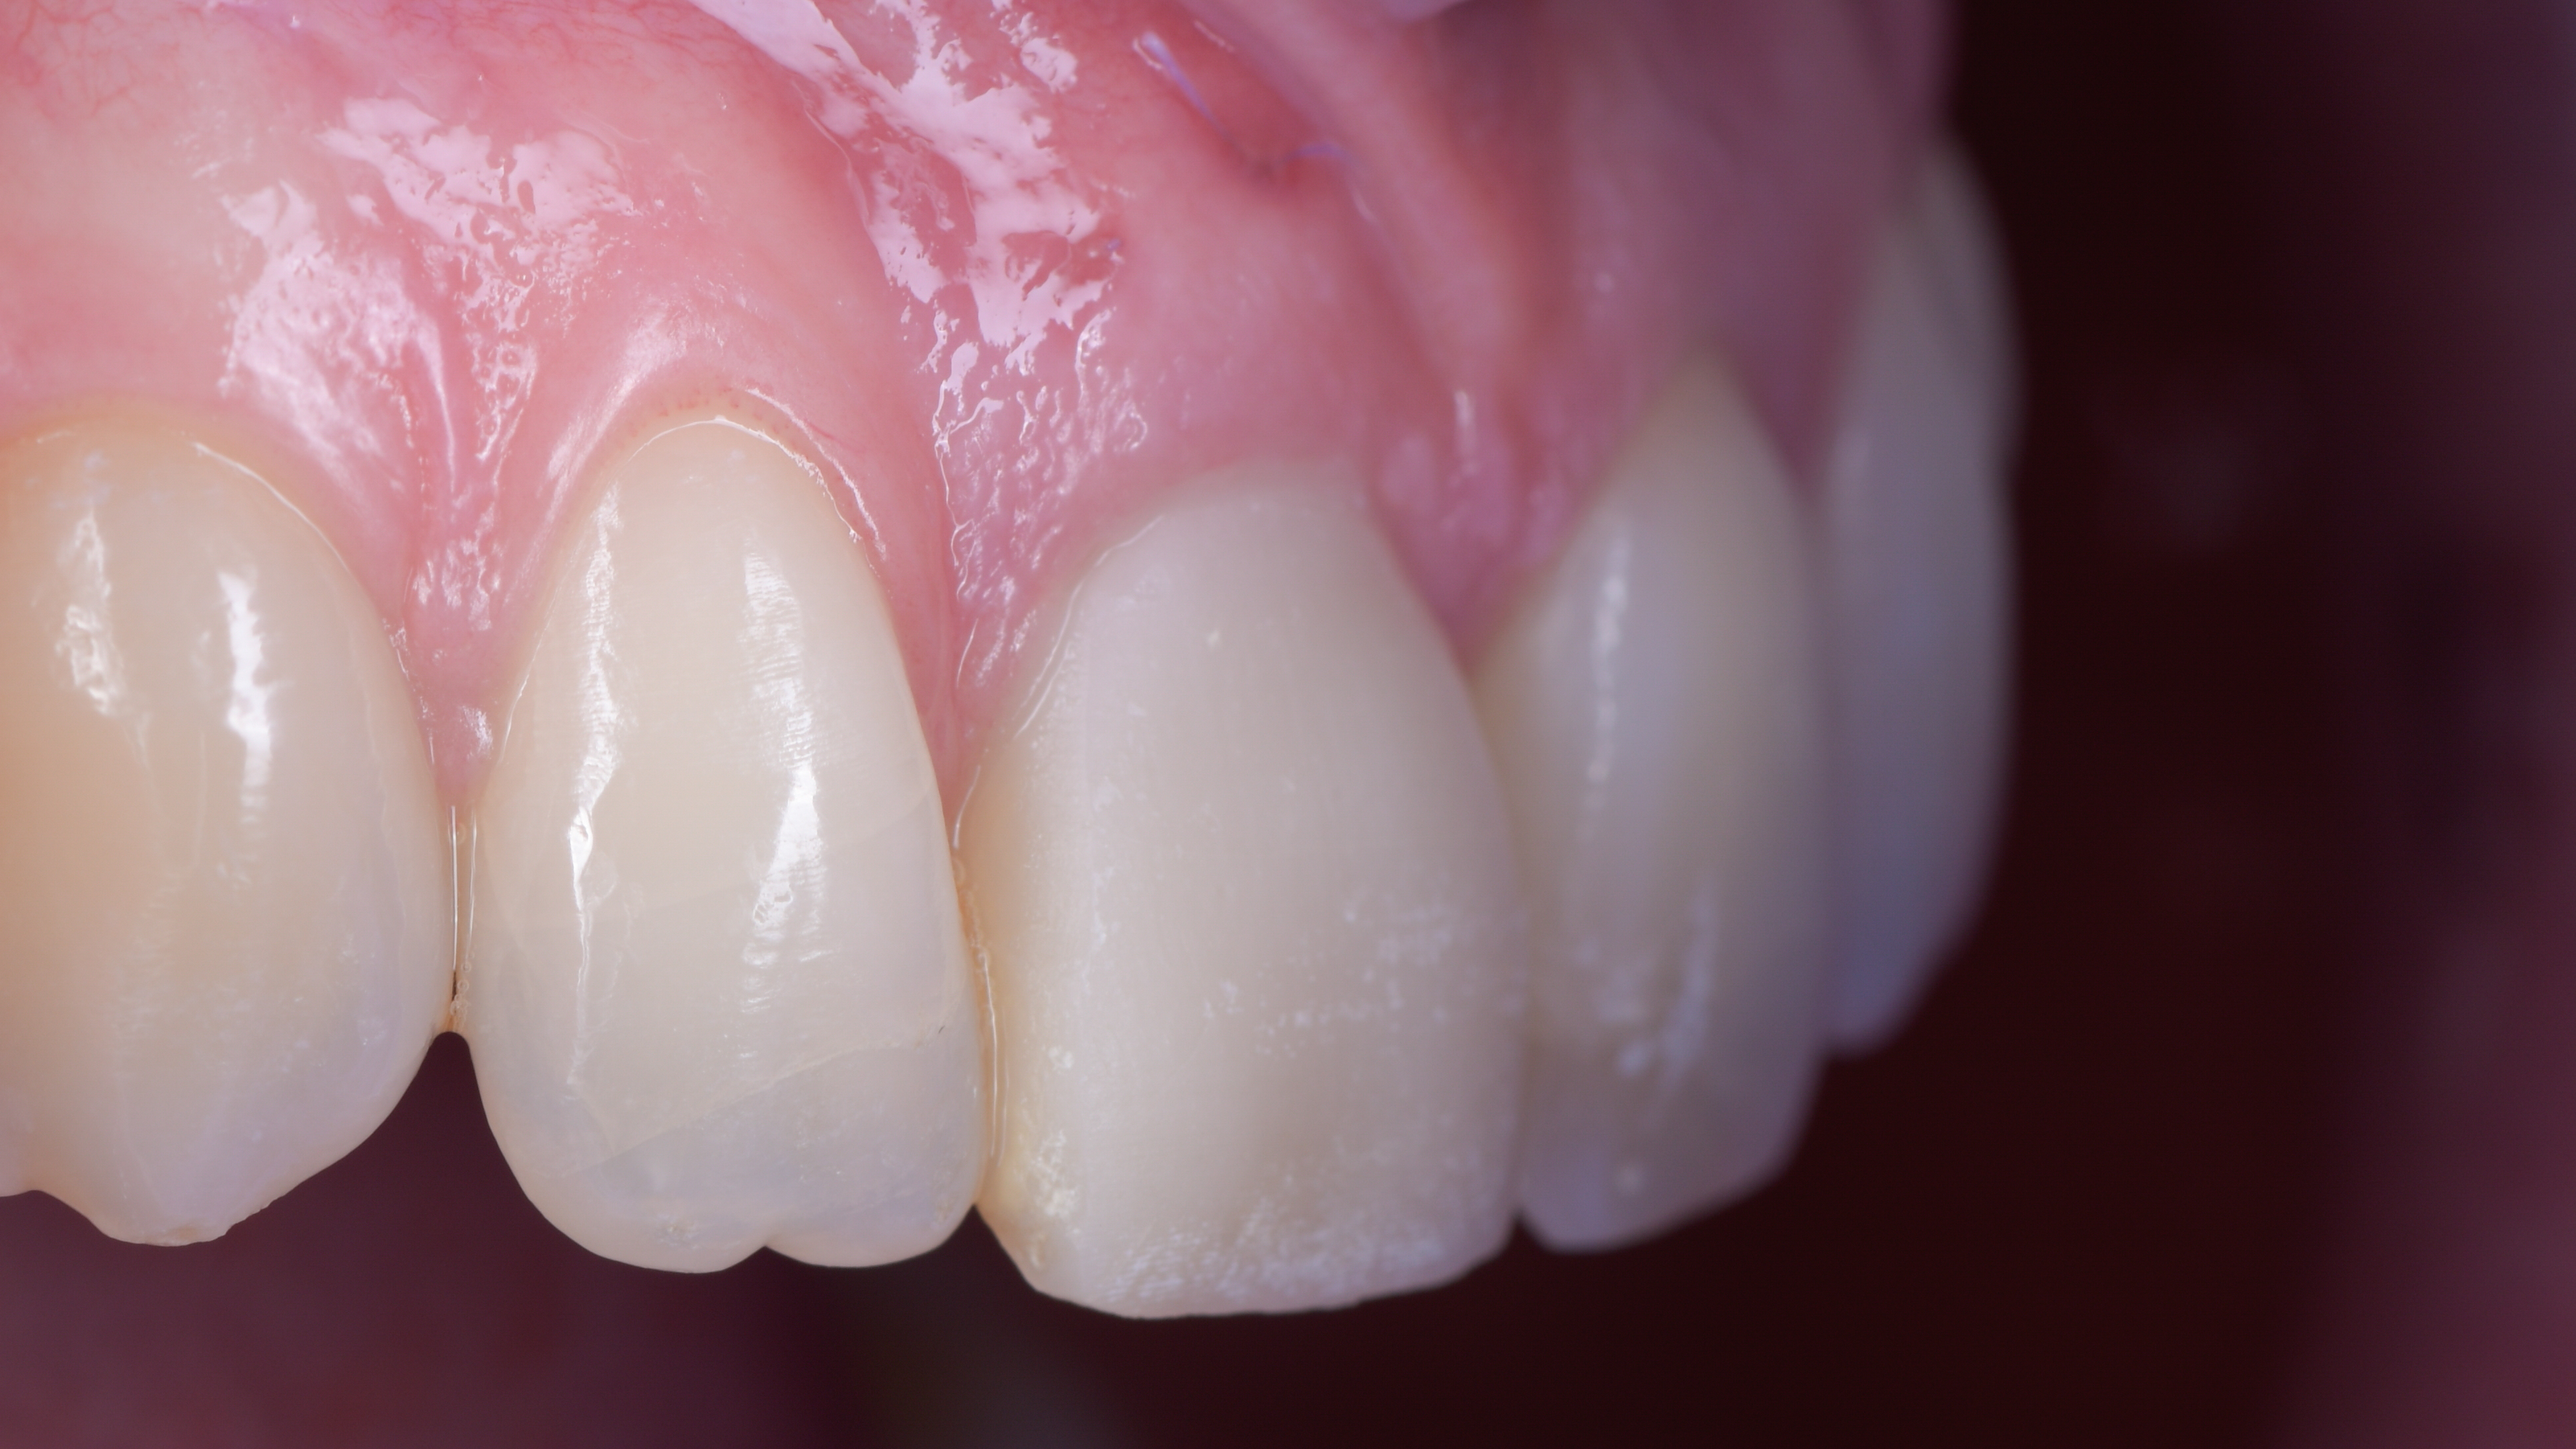

Nous constatons que la cicatrisation est alors optimale et que la prothèse d’usage s’intègre parfaitement à son environnement (Photo 20).

Intégration des réhabilitations au niveau du sourire de la patiente (Photo 26).